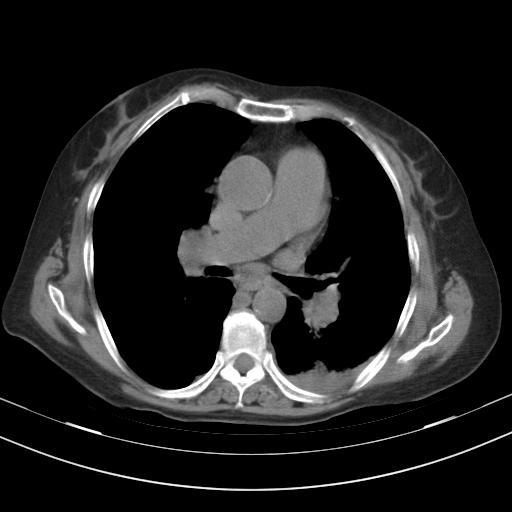

老年女性,嗜睡3天,意识模糊。轻咳,无发热。

1)两肺感染性病变;建议抗炎治疗后复查。2)纵隔淋巴结肿大。3)左侧胸腔积液。

2)纵隔淋巴结肿大。